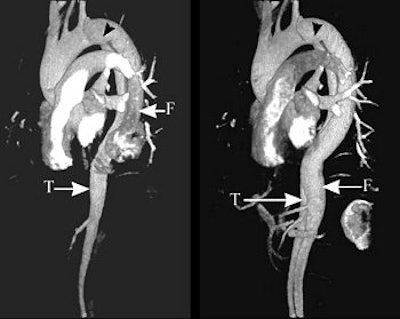

The series of images illustrate the typical manifestations of aortic dissection, including Stanford A (top image, both VR; second image, axial MPR) and Stanford B (third image, arterial phase VR, venous phase VR; fourth image, MIP and VR; fifth image, axial MPR). T = true lumen. F = false lumen. Black arrowhead = entry site. All images courtesy of Qi Liu, Ph.D.

The initial entry site of Stanford B and its relationship with left subclavian artery (top images, both VR).